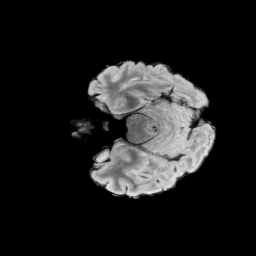

6.3 When does X-Diffusion Fail?

To see when and how X-Diffusion fails, we conducted an experiment on healthy brains (no tumour) using IXI dataset, by running an X-diffusion trained on BRATS brain tumor dataset. Our X-Diffusion achieved a PSNR of 35.86 dB on the IXI dataset despite being trained on the BRATS dataset. We then ran the tumour segmenter on the set of 582 healthy scans and corresponding generated MRIs. The segmenter predicted tumours in 9.9% of the real healthy brains and in 11.3% of the generated brain MRIs. Some of these tumor hallucination examples fron X-Diffusion generation are shown in Figure 10.

This shows how the generated MRIs indeed preserve the tumour information and can act as an affordable and informative pseudo-MRI, before conducting an actual costly MRI examination in hospitals. Given that our model has been trained on brain scans all with tumours, we expect to see hallucinations of tumours in healthy scans. We report two cases of failure of our model in Figure VII. Hallucinations of tumours on healthy samples represent 2% of the test set.